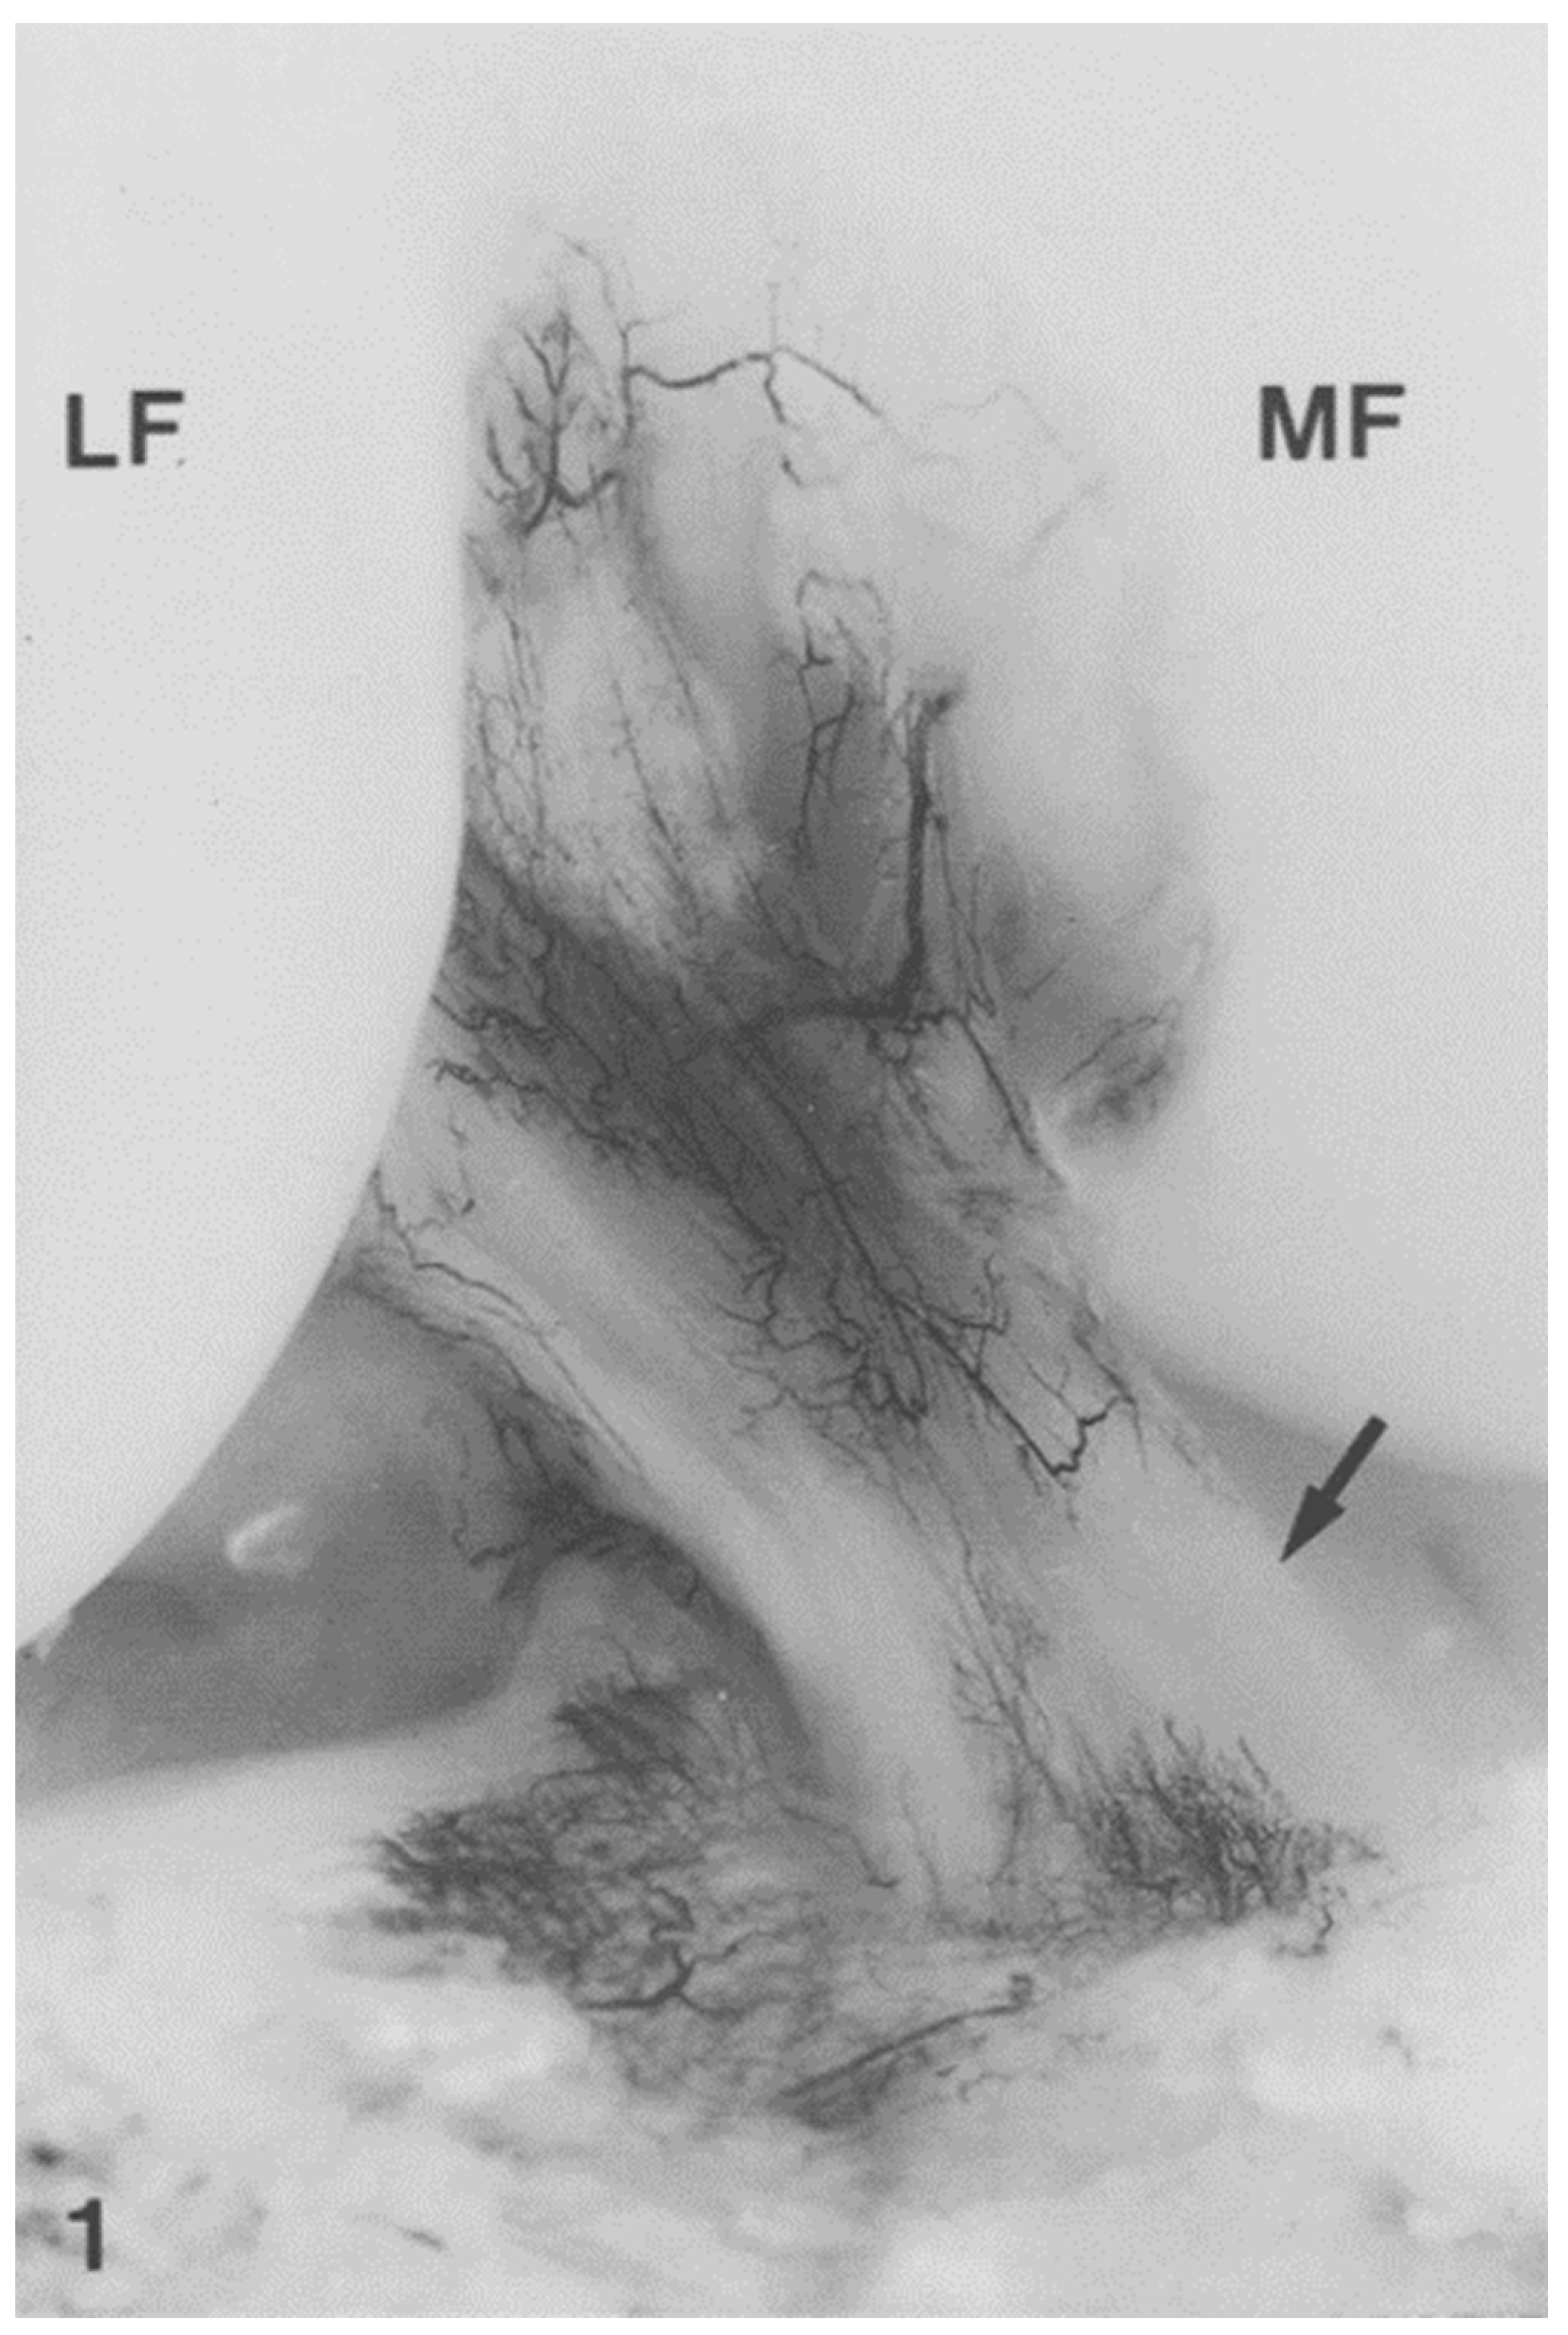

- Scapinelli, R. Vascular anatomy of the human cruciate ligaments and surrounding structures. Clin. Anat. 1997, 10, 151–162. [Google Scholar] [CrossRef]

- Petersen, W.; Hansen, U. Blood and lymph supply of the anterior cruciate ligament: Cadaver study by immunohistochemical and histochemical methods. J. Orthop. Sci. 1997, 2, 313–318. [Google Scholar] [CrossRef]

- Petersen, W.; Zantop, T. Anatomy of the anterior cruciate ligament with regard to its two bundles. Clin. Orthop. Relat. Res. 2006, 454, 35–47. [Google Scholar] [CrossRef] [PubMed]

- Duthon, V.B.; Barea, C.; Abrassart, S.; Fasel, J.H.; Fritschy, D.; Ménétrey, J. Anatomy of the anterior cruciate ligament. Knee Surg. Sports Traumatol. Arthrosc. 2006, 14, 204–213. [Google Scholar] [CrossRef]